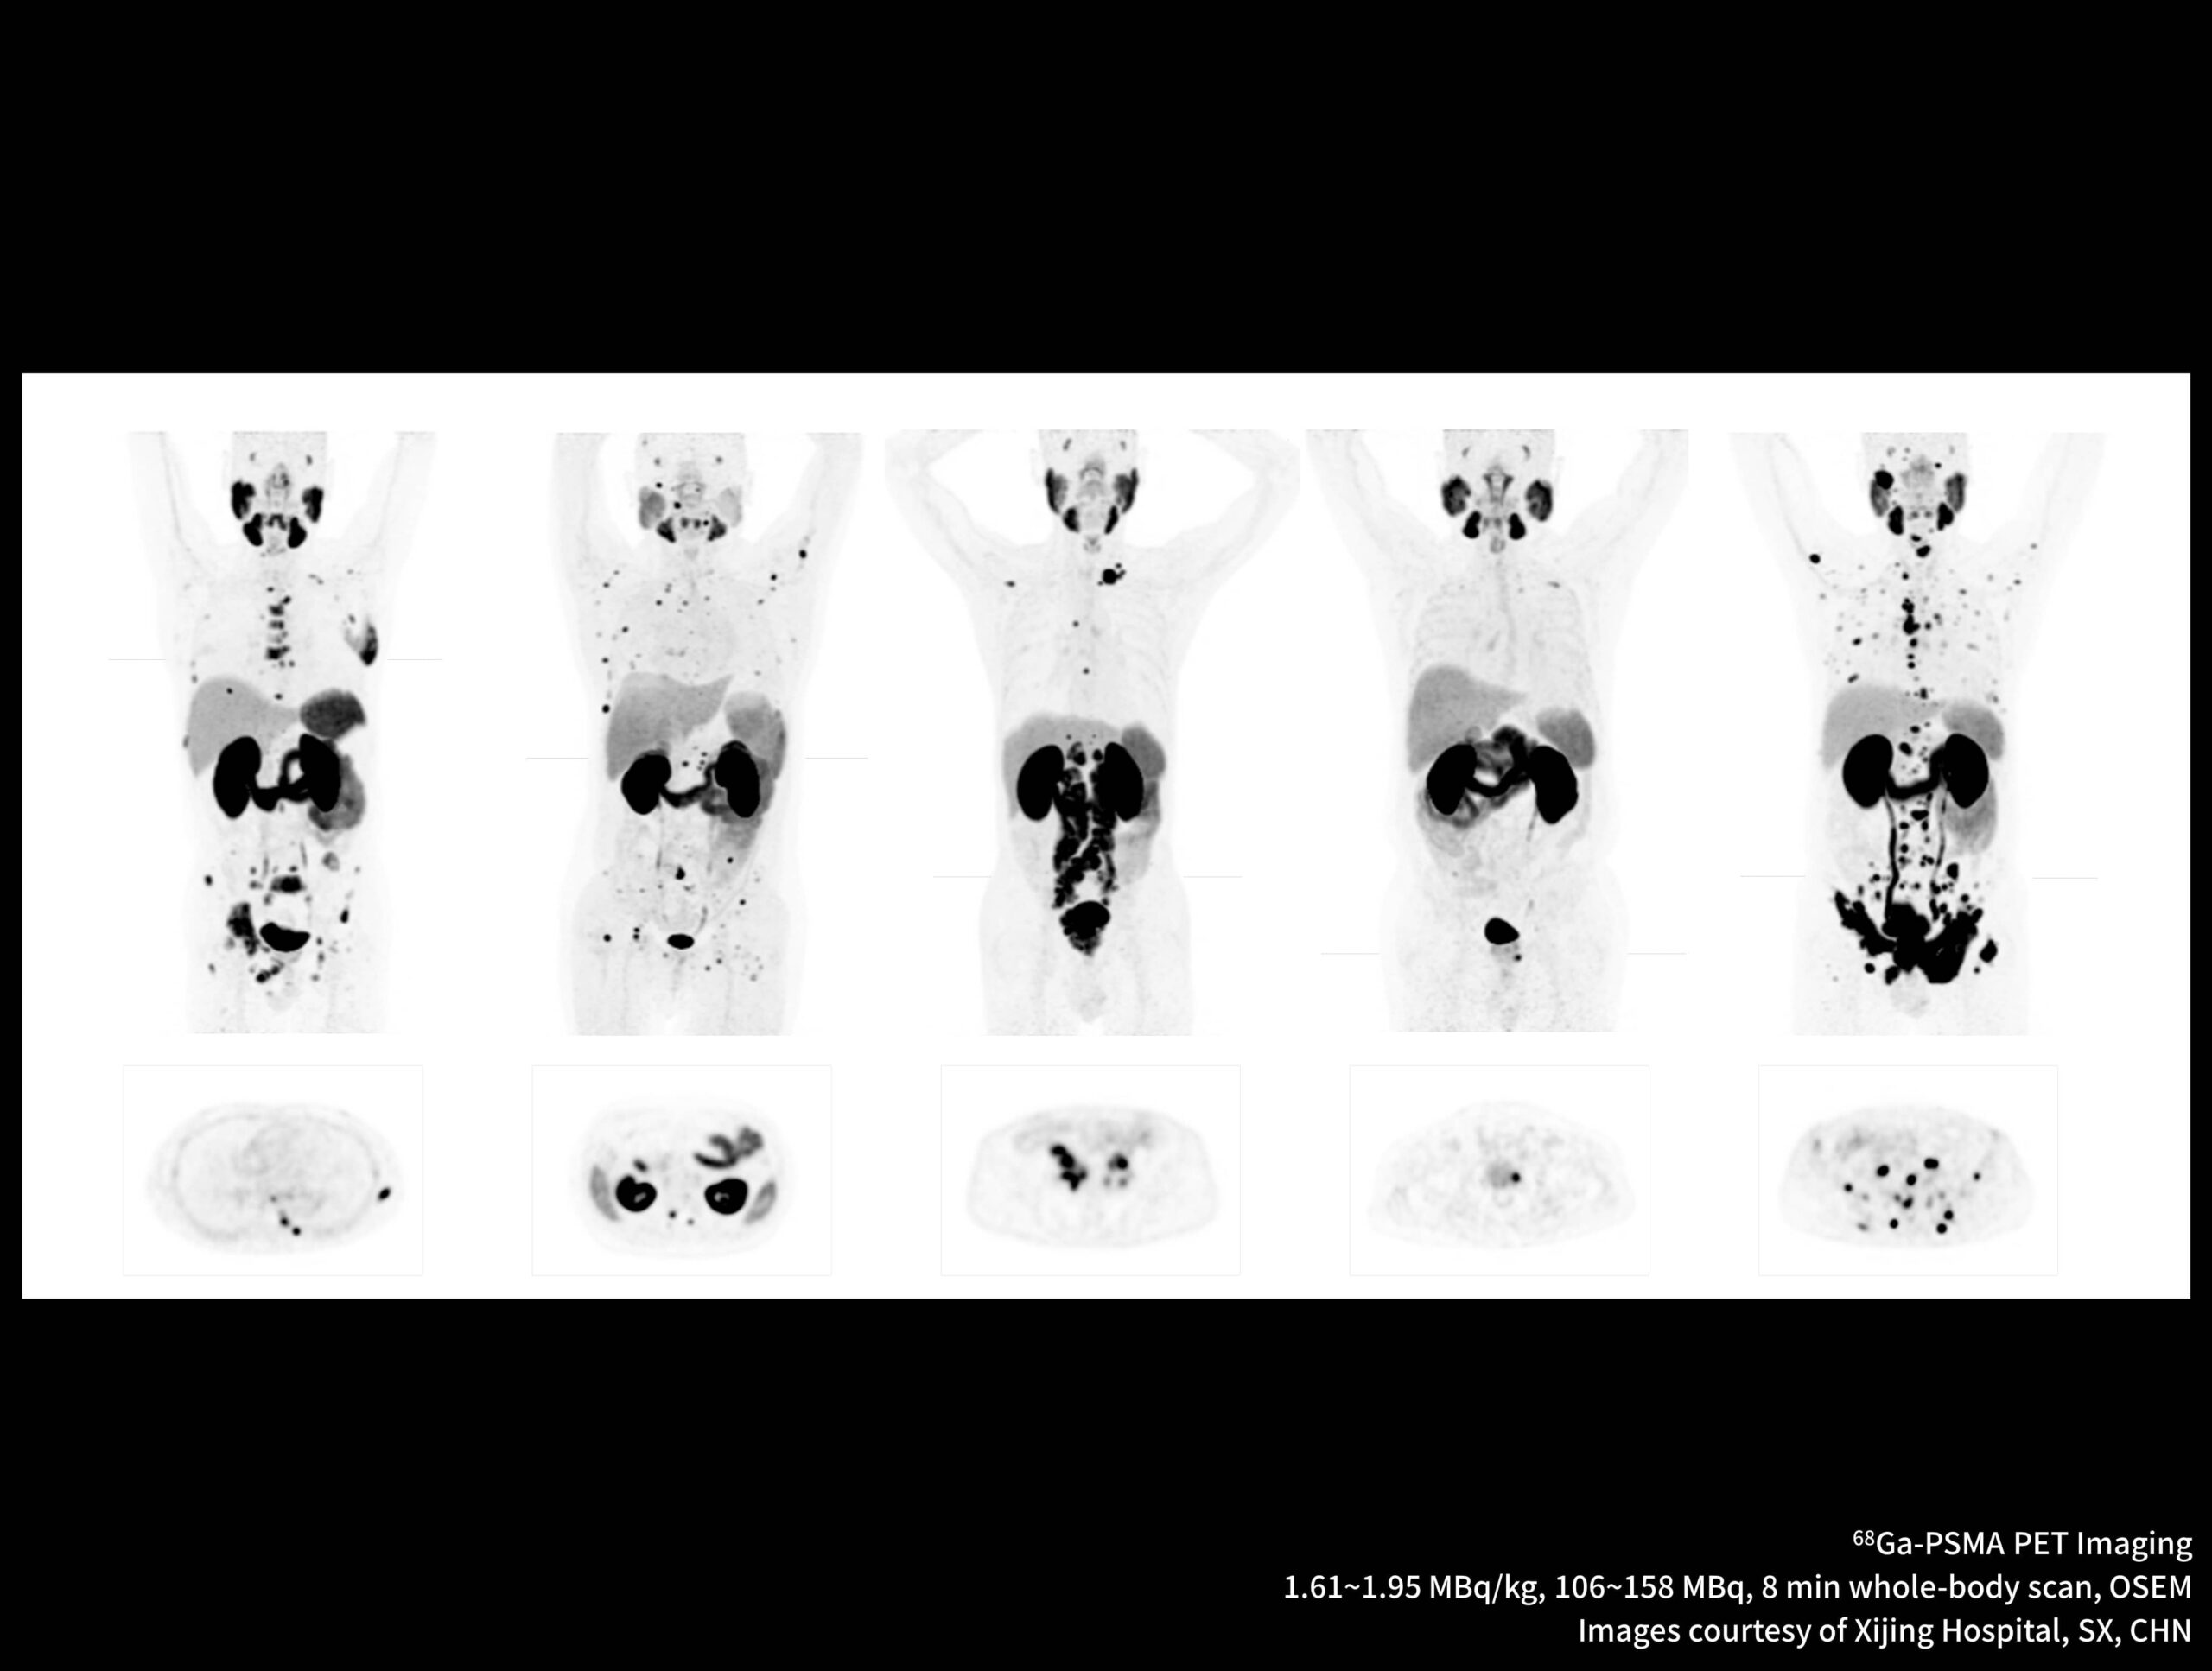

Imagistică de înaltă rezoluție obținută cu radiotrasor marcat cu galiu la doză redusă